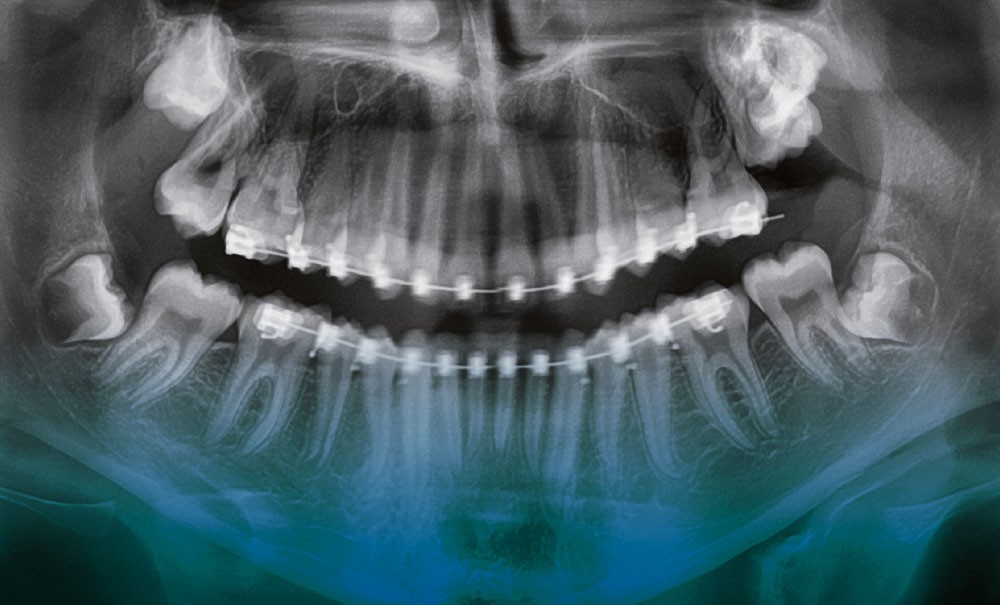

Les dents de sagesse sont les troisièmes molaires : 18, 28, 38, 48 selon la nomenclature. À l’adolescence, elles peuvent être incluses (non visibles en bouche car recouvertes par la gencive et l’os) ou semi-incluses (partiellement visibles).

Les dents de sagesse font régulièrement l’objet d’extraction. C’est le cas lorsque l’espace disponible en arrière des deuxièmes molaires est insuffisant pour leur éruption, lorsqu’elles occasionnent des symptômes répétés à type d’inflammation ou d’infection de la gencive en regard (péri-coronarite) ou lorsqu’elles provoquent ou risquent de provoquer une carie sur la dent adjacente (deuxième molaire).

Cependant, il est parfois nécessaire d’intervenir plus tôt. C’est notamment le cas lorsque la dent de sagesse représente un obstacle à l’éruption de la deuxième molaire (fig. 1 et 2). Le cas échéant, un dégagement chirurgical avec collage d’une attache sur la deuxième molaire est souvent nécessaire, suivi d’une traction orthodontique.